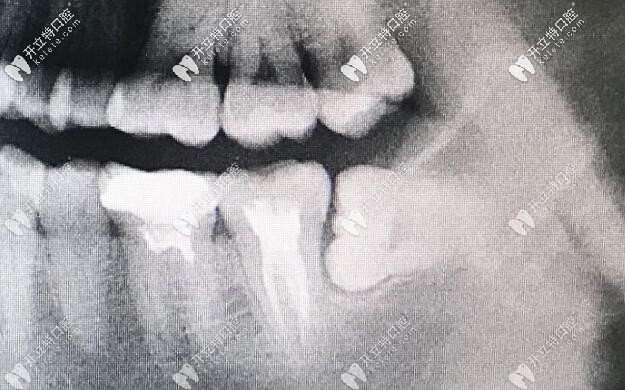

1.口腔檢查,需要拍攝X光片

2.各種錯(cuò)位牙、阻生牙和埋伏牙出現(xiàn)癥狀者。